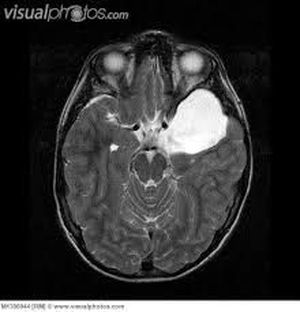

Arachnoid cysts are cerebrospinal fluidcovered by arachnoidal cells and collagen that may develop between the surface of the brain and the cranial base or on the arachnoid membrane, one of the three meningeal layersthat cover the brain and the spinal cord.Arachnoid cysts are a congenital disorder and most cases begin during infancy; however, onset may be delayed until adolescence. Arachnoid cysts may also be classified as primary (congenital) or secondary (acquired) Signs and Symptoms ------------------------------------- Patients with arachnoid cysts may never show symptoms, even in some cases where the cyst is large. Therefore, while the presence of symptoms may provoke further clinical investigation Symptoms vary by the size and location of the cyst(s), though small cysts usually have no symptoms and are discovered only incidentally. On the other hand, a number of symptoms may result from large cysts CAUSES ------------------------ The exact cause of arachnoid cysts is not known. Researchers believe that most cases of arachnoid cysts are developmental malformations that arise from the unexplained splitting or tearing of the arachnoid membrane. Diagnosis --------------------- Diagnosis is principally by MRI Treatment -------------------- Most arachnoid cysts are asymptomatic and do not require treatment. Treatment may be necessary when symptomatic.A variety of procedures may be used to decompress (remove pressure from) the cyst. Surgical placement of a cerebral shunt: *An internal shunt drains into the subdural compartment. *A cystoperitoneal shunt drains to the peritoneal cavity. *Fenestration:Craniotomy with excision *Pharmacological treatments may address specific symptoms such as seizures or pain.